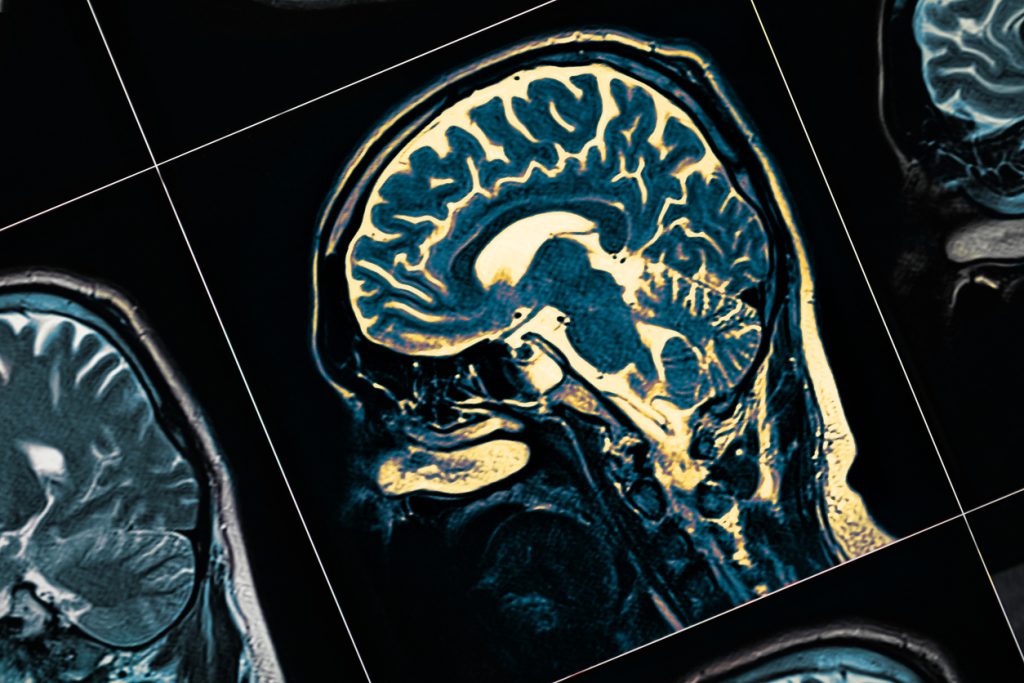

Apneea în somn și boala Parkinson: când respirația îți poate afecta creierul pe termen lung

Apneea în somn este mai mult decât o simplă tulburare a somnului cu sforăit și oboseală de zi. Cercetările recente sugerează că există o legătură semnificativă între apneea în somn și boala Parkinson. Astfel, conform studiilor, afecțiunea respiratorie nocturnă ar putea crește riscul de a dezvolta o boală neurodegenerativă pe termen lung.

Dar cele mai noi dovezi sugerează că efectele apneei nu se opresc la nivelul inimii sau metabolismului. Ele pot implica chiar și sănătatea creierului.